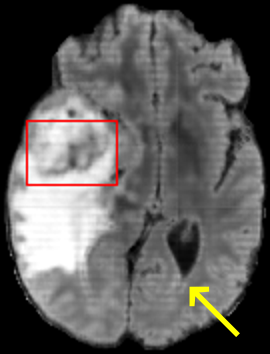

To test the impact of the iterative refinement on YODA’s translation quality, we compared regression and diffusion sampling on the RS data and present additional generation examples in Fig. 6. We observe that diffusion sampling visually resembles the appearance of the acquired images. Regression sampling preserves key anatomical features – the GM/WM boundary, WMHs (Fig. 4), the outline of the pallidum (Fig. 6) – but omits many high-frequency features. To investigate whether iterative refinement during diffusion sampling adds relevant and systematic medical information or only imitates acquisition noise, we performed ExpA sampling, i.e. averaging the output of several ( or ) diffusion trajectories. We observed a gradual loss of high-frequency details when increasing the (see also the supplementary video), indicating that the effect of the iterative refinement is non-systematic. For , the images are visually almost indistinguishable from the initial regression solution (see the supplementary video, and Fig.4 and 6). We directly compared the synthesis results of ExpA () and regression sampling quantitatively and found the differences to be minimal (SSIM: 99.73%, PSNR: 45.30 dB), i.e. diffusion sampling approaches the initial regression solution for a high . The quantitative analysis of the image quality (Tab. 1) showed that diffusion sampling impairs the assessed SSIM and PSNR in comparison to regression sampling for both the in- and external test sets, which we attribute to noise generation (Sec. 3.1). In turn, ExpA averages improved both metrics and, for , performed mostly on par with the regression solution in both test sets in terms of SSIM, while the PSNR in the RS was slightly increased (Tab. 1). However, we observed that ExpA sampling YODA improves the replication of systematic 3D low-frequency image intensity drifts (bias fields) due to the 3D synchronization in 2.5D diffusion sampling. Yet, this apparent advantage did not generalize to the external MBB dataset, as bias fields are MR protocol-specific.

To assess the suitability of YODA-generated images for WMH detection independent of segmentation tools, we also calculated the CNR (15) of WMHs. This confirmed that the contrast of WMHs is preserved in the regression images, whereas we noted slightly reduced WMH contrast for diffusion and ExpA-sampled images (Tab. 1).

In the MRI CT translation in the Gold Atlas dataset (Fig. 8), major bones and muscles are translated faithfully. Yet, diffusion sampling leads to some inaccuracies in the outline of bones and hallucinations of the textures of inner organs. Conversely, regression sampling faithfully translates bones while still blurring the inner organs and generating artifacts. This indicates that rendering CTs is under-defined by the given MRI guidance alone.

When analyzing the RS synthesis results (Fig. 4), we noted that most reference methods strive to imitate realistic images, but several artifacts can be observed such as hallucinated WMHs (SynDiff) and salt-and-pepper noise (SynDiff, I2I-Mamba, ResViT).

However, we observed some missing small WMHs (third row, Fig. 9) in the synthetic FLAIR images. Due to the weak input signal, translating small WMHs in inherently difficult and, thus, omitting these WMHs can be seen as conservative. In contrast, a more speculative translation bears the risk of false-positive, hallucinated WMHs (compare e.g., SynDiff, Fig. 4).

In Brats, we observed one case with FLAIR hyper- rather than hypo-intense tumor cavity (Fig. 9, fifth row).